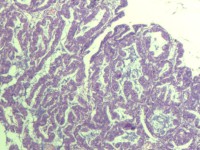

性别

女

年龄

55岁

临床诊断

异常子宫出血

一般病史

阴道不规则出血1月

标本名称

子宫内膜

大体所见

灰白色组织1堆、4*3.4*2.2CM大。

能诊断癌吗

子宫内膜样腺癌